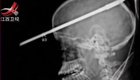

男孩被魚叉戳穿腦顱 奇跡存活